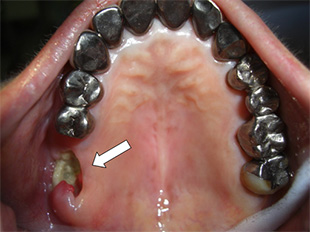

抗がん剤の副作用によって、口の中の感染症(重症の口内炎、カンジダ症)や、歯肉出血、虫歯や歯周病の悪化、併用薬剤による難治性の顎骨壊死(図6)などが起こり易くなります。

【図6】抗がん剤治療中に生じた顎骨壊死